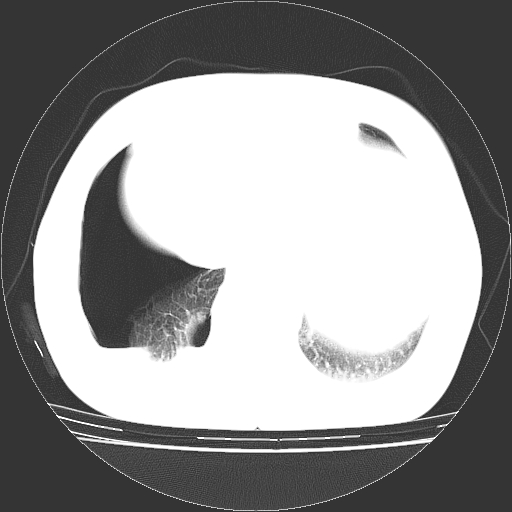

以下是引用zhangzhongshou在2008-3-22 12:52:00的发言:[br]1、右侧液气胸。[br]2、腹水。建议进一步检查。

以下是引用鲁巨ct在2008-3-22 14:10:00的发言:[br]1、右侧液气胸,右中下叶节段性不张。[br]2、腹水,建议上腹部ct检查

以下是引用zjzjr在2008-3-22 17:19:00的发言:[br]1、右侧液气胸,右下叶节段性不张。[br]2、腹水,建议上腹部ct检查